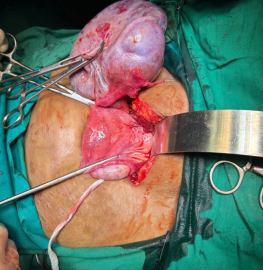

Big size fibroid surgery done by Dr Nupur Das in 16 years young girl.